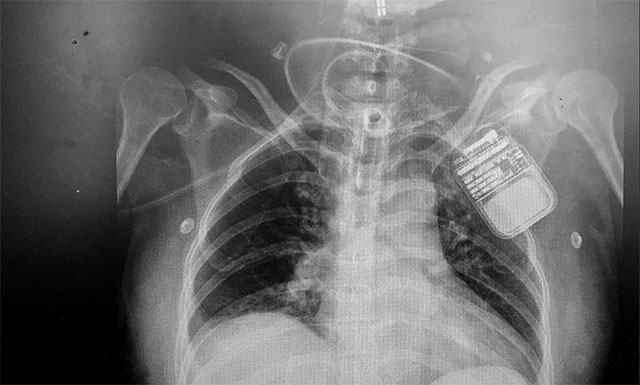

脊髓神经电刺激术是通过微创手术将电极置入脊髓上方,以脉冲电流刺激脊髓神经,增加脑血流、脑代谢,而且还能激活脑干网状上行系统,这样不仅能改善脑循环、缩小缺血灶,还能兴奋大脑皮层,促进患者神志清醒。

该技术优势明显,具有微创、可逆,并可依据患者病情需要进行治疗参数的调节,实现个体化定制,同时可有效改善患者全身循环水平等优势,对长期昏迷特别是“植物人”患者有很好的促醒作用。

▲ 电刺激器顺利置入患者脊髓上方